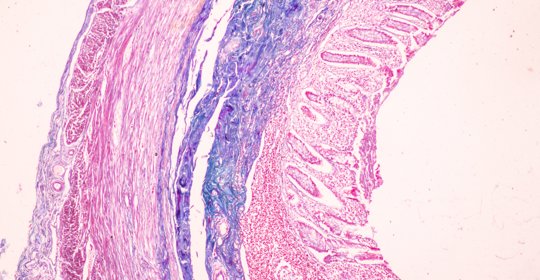

橫結腸息肉:便血腹痛與子宮息肉內分泌失調不同管理